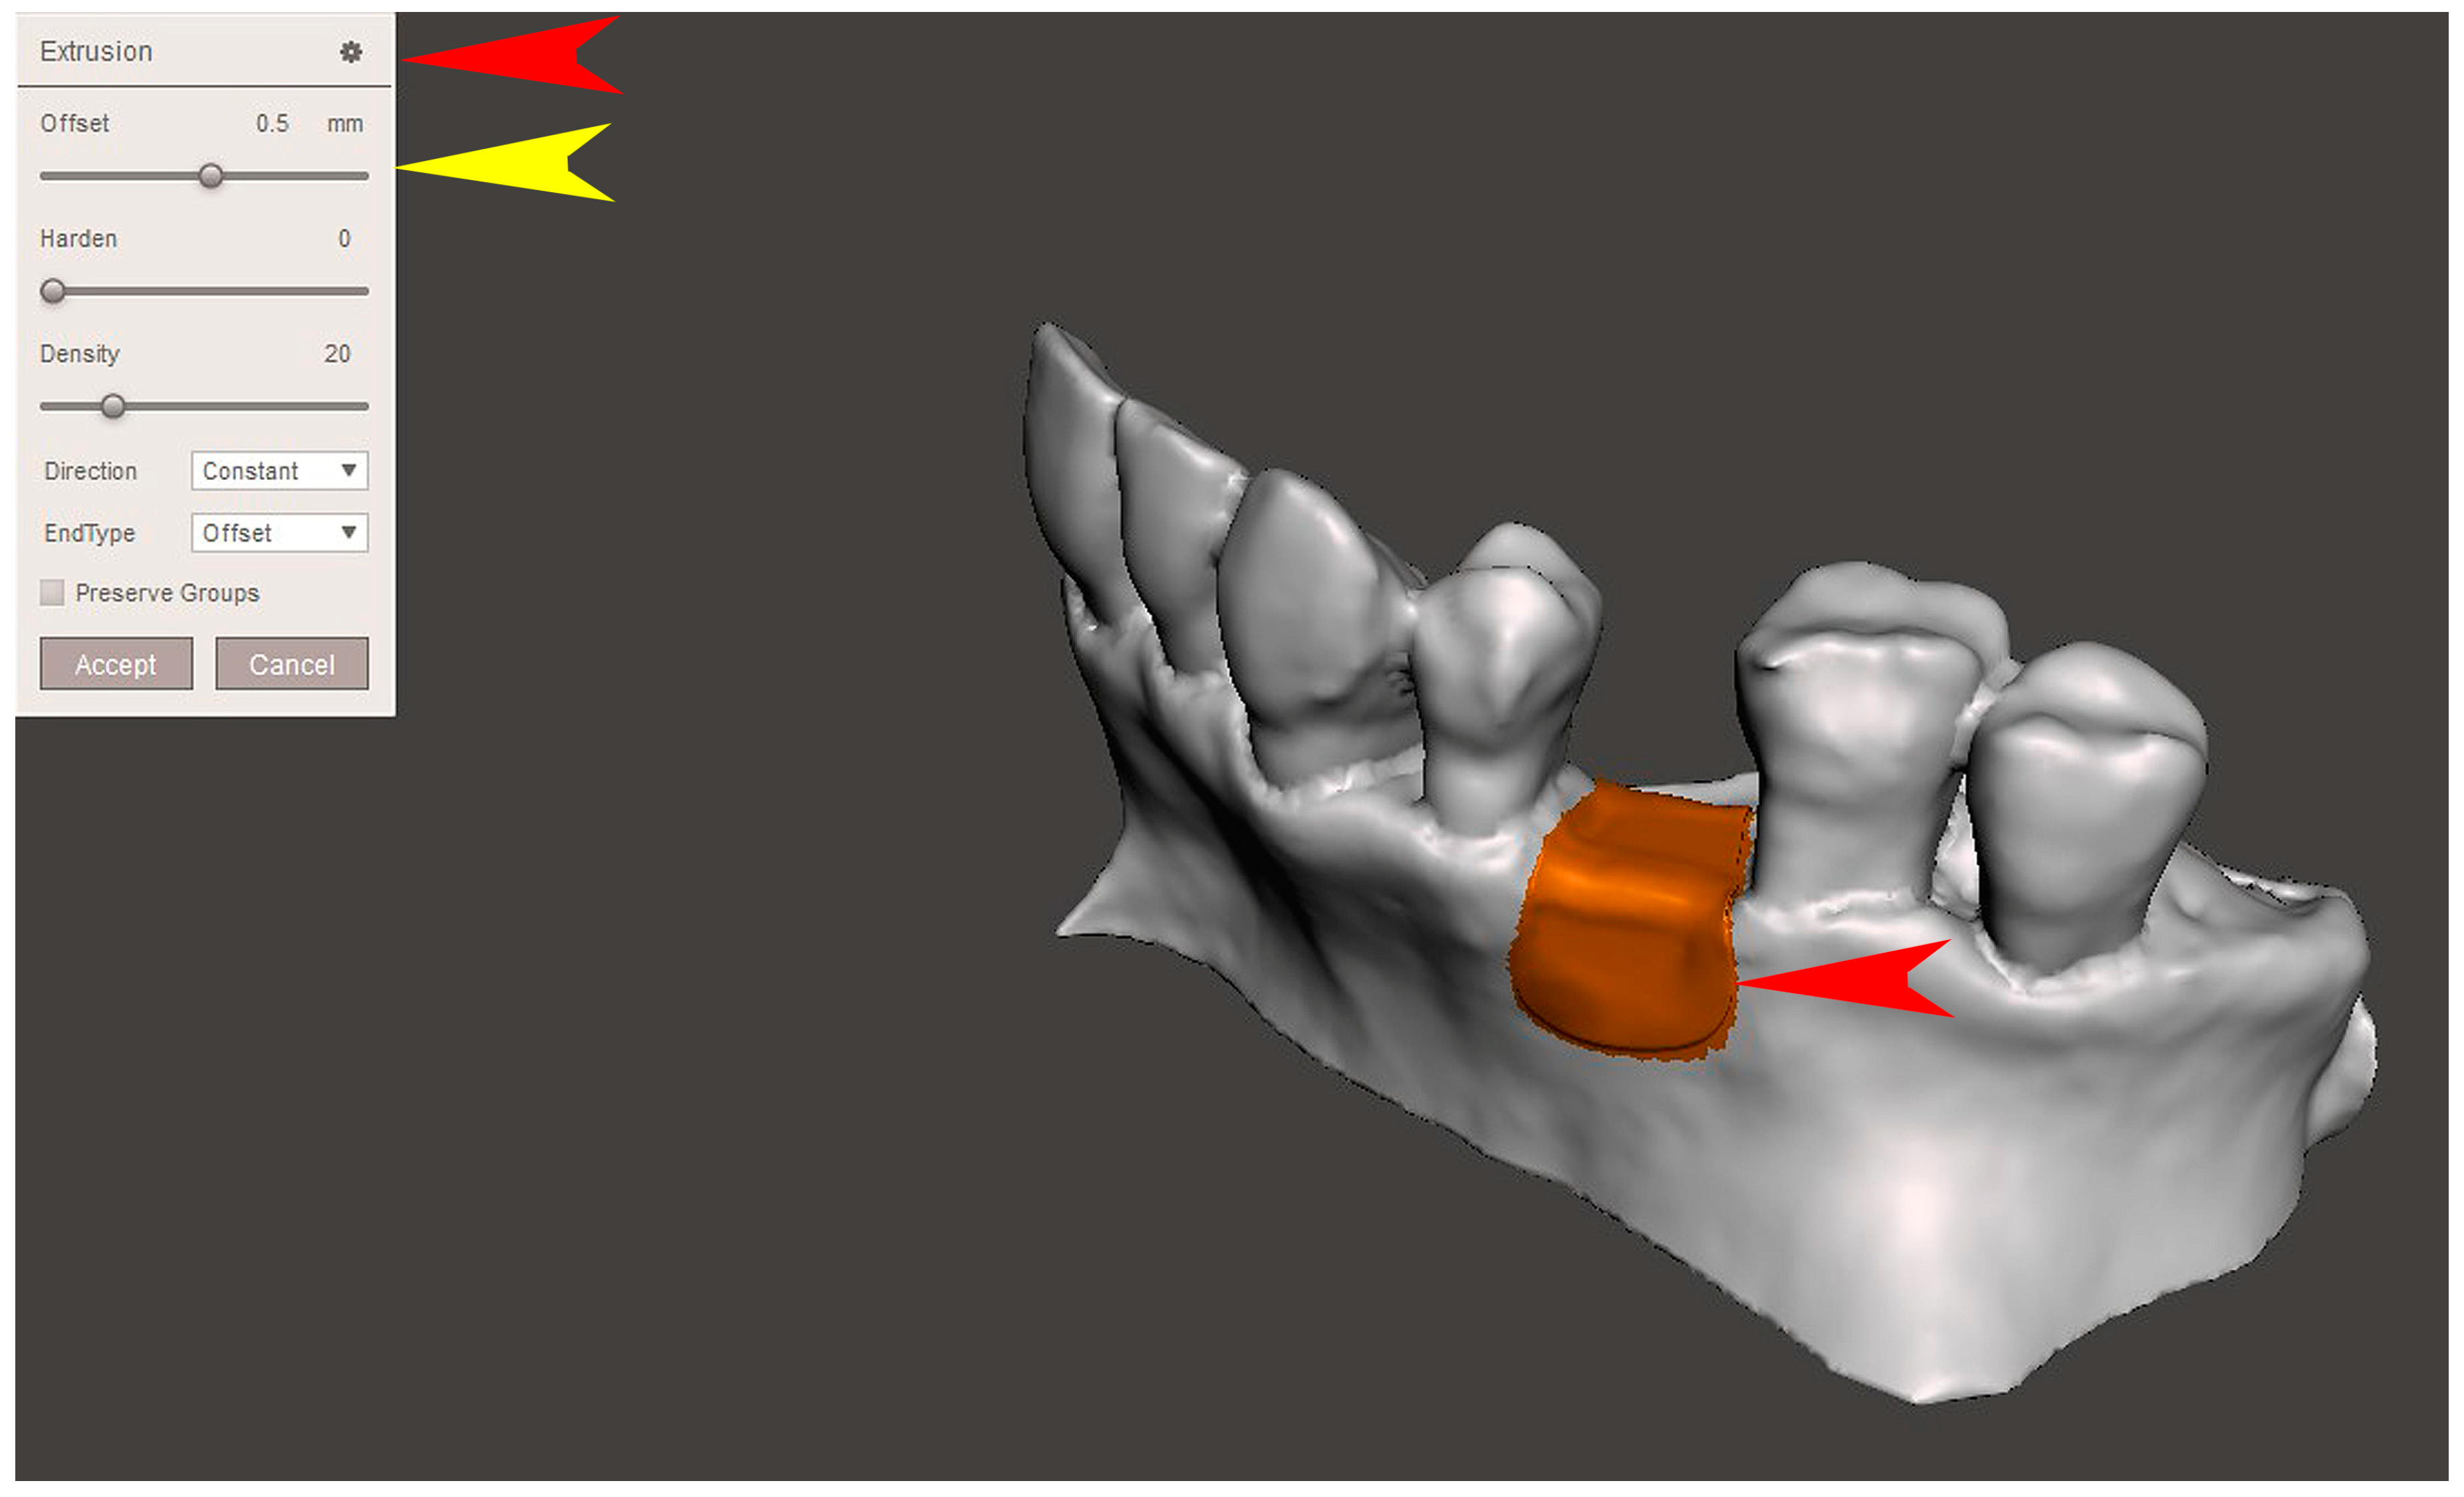

2.2. GBR Simulation and Mesh Design